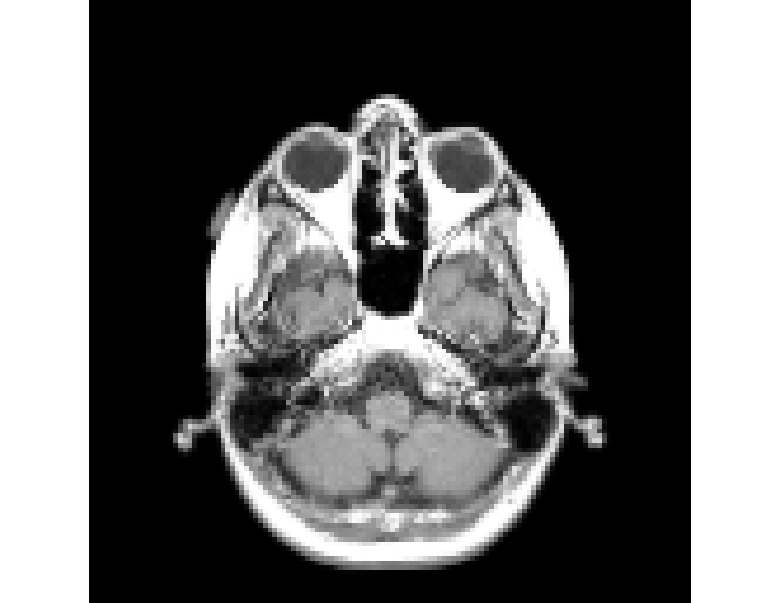

RANDSMAPs are evaluated against three mass-preserving benchmark examples with varying scalability: a moderate-dimensional 1D traffic density dataset from the Lighthill-Whitham-Richards (LWR) hyperbolic PDE; a high-dimensional 2D gray-scale MRI image dataset with sparse observations; and a high-dimensional 2D pedestrian density dataset governed by the Hughes crowd dynamics PDEs. Additionally, two classic low-dimensional manifold learning examples without inherent mass conservation (the classic 33-dimensional Swiss roll and S-curve projected in 2020 dimensions) are included to establish a baseline for RFNN decoder performance. In all examples, RANDSMAPs are compared against the DDM and kk-NN decoders. To ensure fair assessment, all decoders operate on the same low-dimensional embedding/encoding, obtained here via the DM algorithm, though each decoder is, in principle, compatible with any embedding.

For each problem, the performance of each decoder is evaluated based on (i) reconstruction accuracy, (ii) computational cost, and (iii) conservation accuracy. We quantify the reconstruction accuracy of each decoder by its relative L2L_{2} and LL_{\infty} reconstruction error across the training and testing sets, 𝒳tr\mathcal{X}_{tr} and 𝒳ts\mathcal{X}_{ts}, respectively. To assess computational cost, we recorded the computational times required for both training and inference. Training time includes encoder training (DM algorithm), hyperparameter tuning (of a single parameter for each decoder) over a held-out validation set 𝒳vl\mathcal{X}_{vl}, and decoder training. Inference time covers the complete end-to-end pipeline on the testing set 𝒳ts\mathcal{X}_{ts}, including the encoding to obtain the embedding and the decoding to reconstruct the entire testing set. To assess conservation accuracy, we quantify the pointwise deviation from the exact sum-to-one invariant in Eq. (6). As the RANDSMAP decoder is designed to preserve the sum-to-one invariant by construction, we verify this numerically and demonstrate that it maintains competitive reconstruction performance. To account for the stochasticity inherent to the random feature construction, all reported results for the RANDSMAP and RFNN decoders are averaged over 100 independent runs. The complete implementation details, including dataset generation, train/validation/test splits, feature construction sampling procedures, hyperparameter grids, and solver specifications, are provided in Appendix D.

From the full dataset, we randomly split the data into training and validation sets 𝒳tr\mathcal{X}_{tr} and 𝒳vl\mathcal{X}_{vl}, each containing N=2000N=2000 points, with the remaining 80008000 points reserved for the testing set 𝒳ts\mathcal{X}_{ts}; a visualization of the density profiles in 𝒳tr\mathcal{X}_{tr} is shown in Fig. 3(a). Since the ambient space where the data lie is 400400-dimensional, we project them onto three summary statistics of the density distributions: the mean position μx\mu_{x}, variance σx2\sigma_{x}^{2}, and skewness γx\gamma_{x}. This low-dimensional projection reveals an underlying manifold structure arising from the conservation law.

We next employed the DM algorithm with α=0\alpha=0 and w1=1w_{1}=1 to the training set to obtain a d=2d=2-dimensional embedding. The resulting DM coordinates yi2y_{i}\in\mathbb{R}^{2} are shown in Fig. 3(b), colored by the mean position μx\mu_{x}. The dimensionality d=2d=2 was selected based on a clear spectral gap after the second eigenvalue (data not shown) and its sufficiency for achieving accurate reconstruction, as demonstrated below.